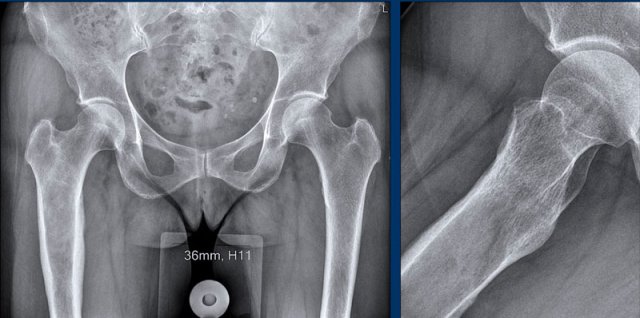

Case

First look at the images.

Then continue reading.

Images

There is an osteolytic, expansile

lesion in the right proximal femur diaphysis.

Adjacent subtle cortical

thickening is present without periosteal reaction.

No frank chondroid matrix is

appreciated on this radiograph.

Conclusion

The differential diagnosis would include chondrosarcoma,

fibrous dysplasia, lymphoma, metastasis and plasmacytoma.

An unenhanced CT could help in

detection of subtle chondroid matrix calcifications in this case. However, we

went straight for MRI.

Treatment consisted of en bloc resection of the proximal femur and reconstruction with an endoprosthesis.

Pathology confirmed a chondrosarcoma grade II.

Chondrosarcomas grade II and III cannot be differentiated based on imaging.

This is a diagnosis made on histopathology.

Therefore, we refer to such lesions as “grade II or higher” in our radiology report.